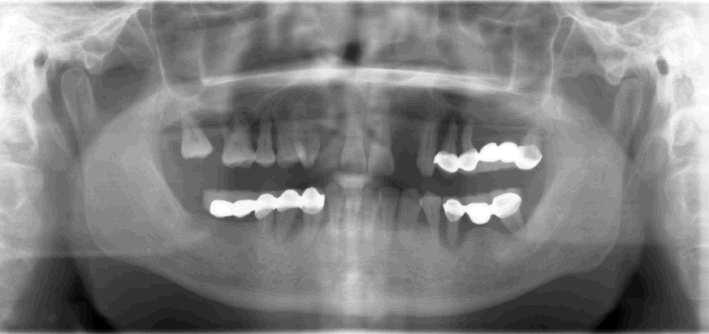

Fig.1 38 year-old male patient presented in 2006 with chief complaint "loose bridges". Exam shows poor oral hygiene and restoration, and advanced periodontal disease. Initial treatment includes removal of grossly nonsalvageables, scaling & root planing, and upper removable partial using #1 as distal abutment. Due to pneumatic sinuses and finance, implants would be placed in the mandible first. | |